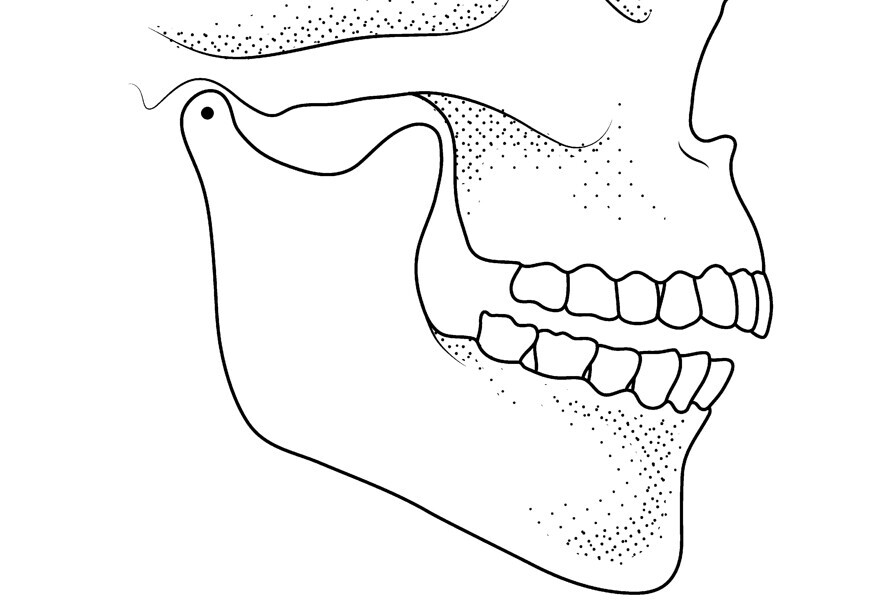

Fig. 4: Mandibular position defined as condylar position and vertical dimension of occlusion.